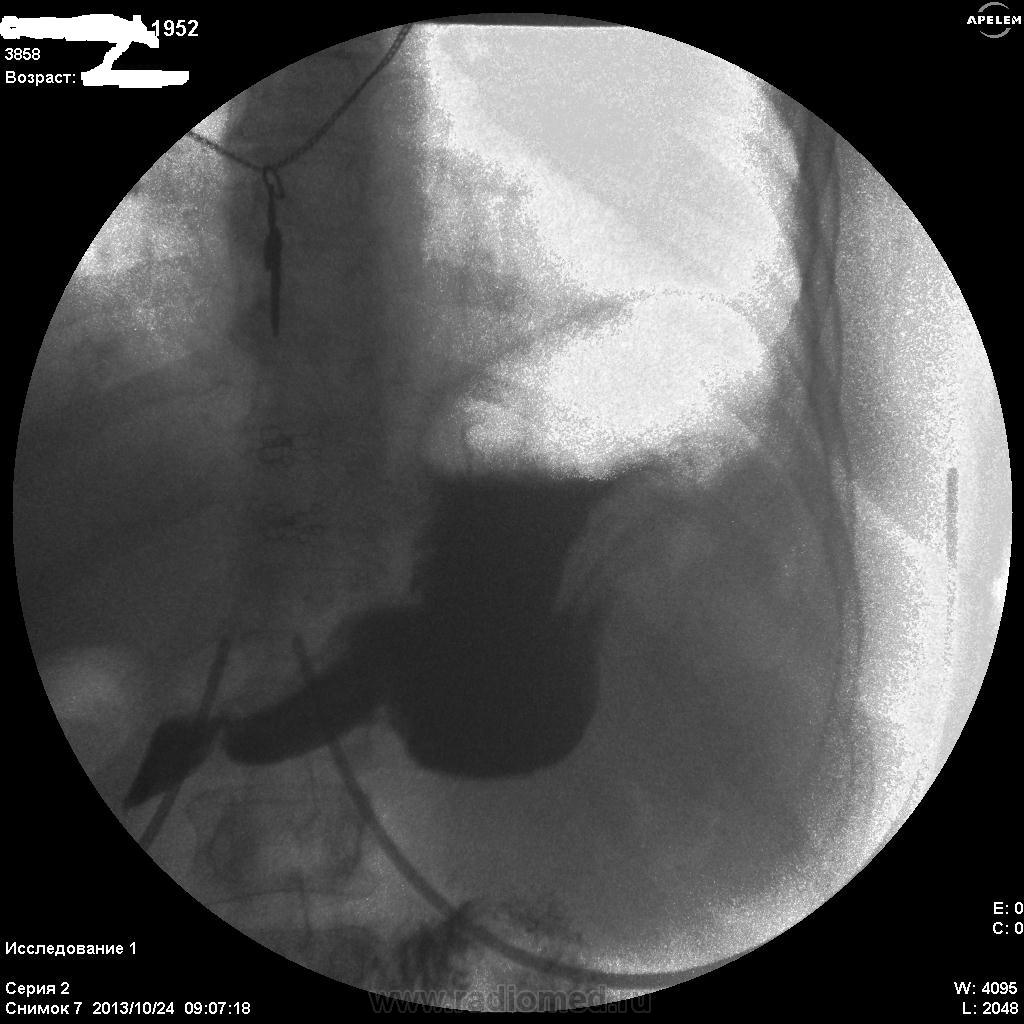

Пилорический отдел плохо выглядит, инфильтративная форма рака может быть. Лежа снимков нет? На что жалуется женщина? Лифчик немного мешает оценивать снимки))

Не сразу заметила дефект наполнения по большой кривизне, все не так с этим желудком

Необходимо уточнять состояние большой кривизны субкардиального отдела и тела (новообразование?), только ЭТИХ снимков явно мало...увы....

По-желудку - расположен косопоперечно, в гипертонусе. Впечатление не полного тугого наполнения. На большой кривизне могут быть и складки, плохо видно. На малой кривизне похоже на 2 ниши, ширина которых преобладает над глубыной, могут быть онкологические, но опять же куда они деваются на последнем снимке... Пилорический отдел либо конически сужен, либо не наполнен адекватно. В общем, можно просто предположить, либо это язвеная болезнь "хроническая" (отсюда деформация желудка и все остальное), либо это онкология (лимфома к примеру). Либо вообще такую картину дает гипертонус, усиленная перистальтика и малое количество контраста. Предложил бы искусственную гипотонию и бария не менее 200 мл.

Жалоб конкретных нет(так,что-то ноет).Еть отрывки кинопетли лёжа,но сегодня не смогу показать.Первый кадр здесь-стоя,потом-с поворотами налево и направо.Я собственно снимки не делаю,пишу кино.В "последующих сериях" деффект сохранялся,на компрессию не реагировал.

Первые три-в орто.Последний-лёжа.

Как вариант, язва (или рубцово-язвенная деформация) по малой кривизне тела желудка с пальцевым вдавлением/"перстом указующим" по б/кривизне антрального отдела.